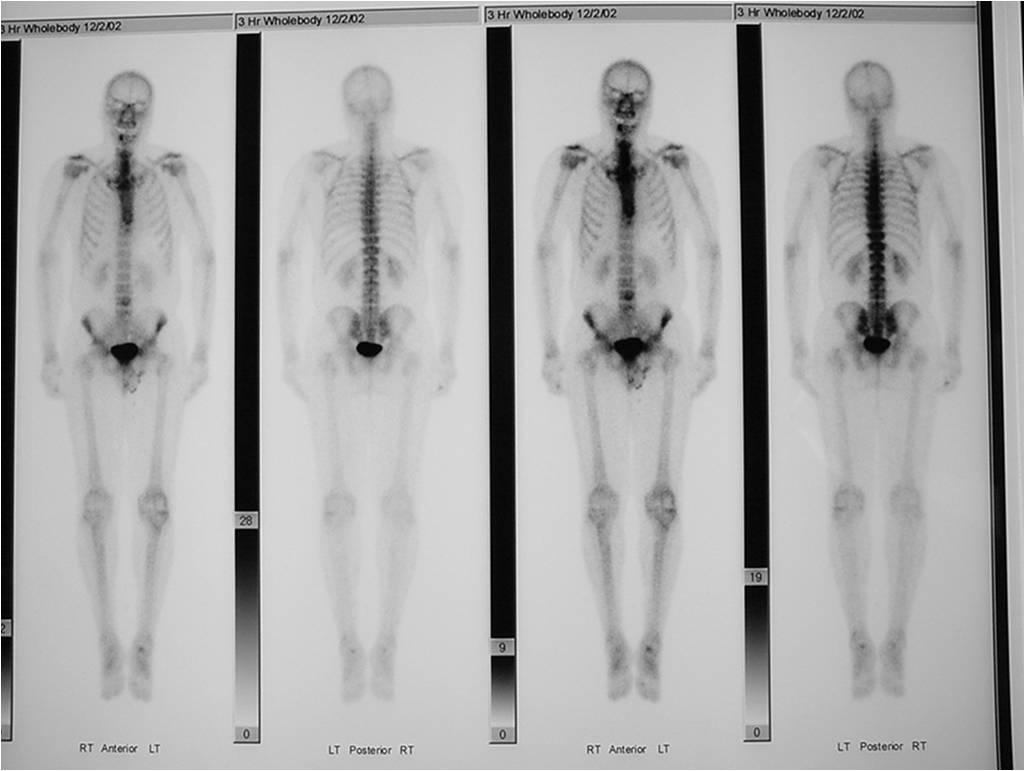

Enchondromas demonstrate increased uptake on a bone scan Most benign cartilage tumors demonstrate uptake that is less than the normal uptake in the ASIS although some may have higher uptake than ASIS

- Bone Scan: Lesion that is hotter than ASIS